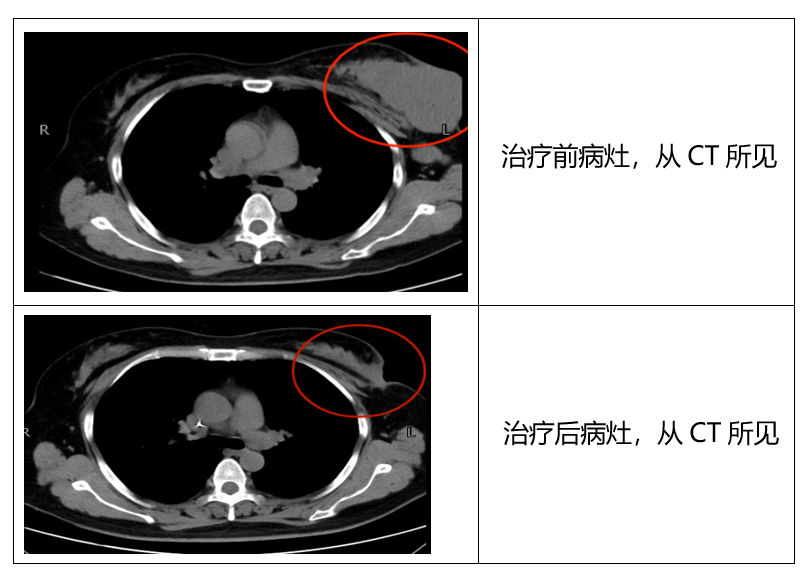

三个月后,经过评估,小张的病灶从直径10厘米左右,缩小至不到2厘米,腋窝淋巴结也明显缩小,达到手术切除条件,转至乳腺科行根治性手术切除。